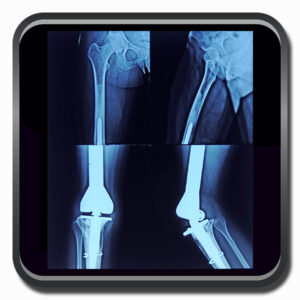

Algumas Cirurgias Complexas realizadas por profissionais da COFIB: